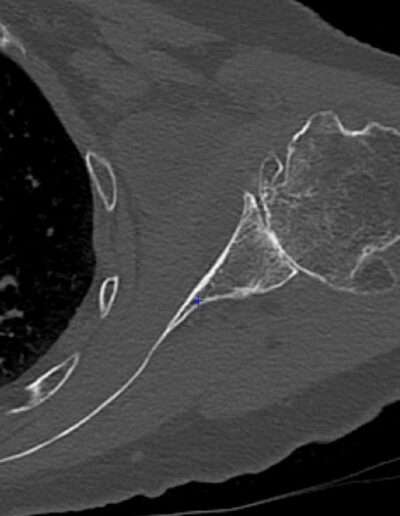

T06: TSA V-Shape

SHOULDER CASE SUMMARY:

Shoulder Left

Patient 81 y/o, Female, right-handed